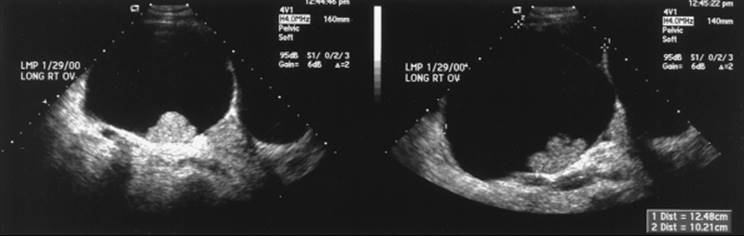

Additionally, solid components are important, because malignant masses often will have solid sections. Several studies have indicated that the incidence of malignancy increases when masses are multiloculated and contain solid areas. Other reports indicate that the most suggestive finding of malignancy is inner wall abnormalities, such papillations, or a solid area. Other important features found on ultrasonography actually can be reassuring, such as calcium found next to fat as noted in dermoid tumors. Thus, adnexal masses that have solid components, inner wall papillations, or nodularity should not be observed further and surgical evaluation would be in order (Fig. 56.2).

FIG. 56.2. Ultrasonographic image of an ovary with internal wall papillations. The final pathology of this ovarian cyst was clear cell adenocarcinoma.